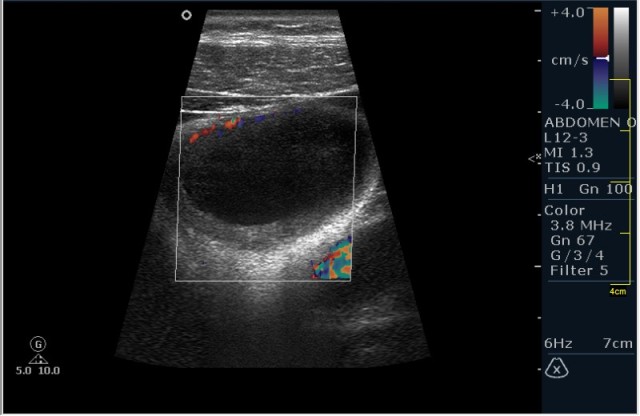

Мужчина 42 года; жалобы на периодические боли в эпигастрии. УЗИ области жёлчного пузыря выявило интересную картину; наблюдается фокальное утолщение стенок пузыря в области тела. Интересно узнать Ваше мнение?

P.S. Ультрасонография при аденомиоматозе выявляет значительное утолщение стенки желчного пузыря с мелкими эхонегативными включениями (синусами). В ряде случаев визуализируются мелкие гиперэхогенные включения, иногда с акустической тенью или эффектом реверберации – это мелкие конкременты, пузырьки газа, сгустки желчи, расположенные внутри синусов Рокитанского-Ашоффа. С помощью допплерографии определяют васкуляризацию утолщенных стенок желчного пузыря.

Мне интерено, а почему Вы решили что это аденомиоматоз? На представленных сонограммах нет признаков этого заболевания, за исключением фокального утолщения стенки (что крайне не специфично, см. ниже). Если мы не находим пристеночных синусов (Ашоф -Ракитанского) образующихся за счёт неравномерной гиперплазии эпителия ЖП с протрузией эпителия в стенку, и не видим гиперэхогенные фокусы в стенке за счёт кристаллов холестерола; мы не можем выставлять диагноз аденомиоматоз. В нашем случае мы имеем дело с равномерным гипоэхогенным утолщением (см. сонограммы призведённые линейным датчиком с высоким разрешением).